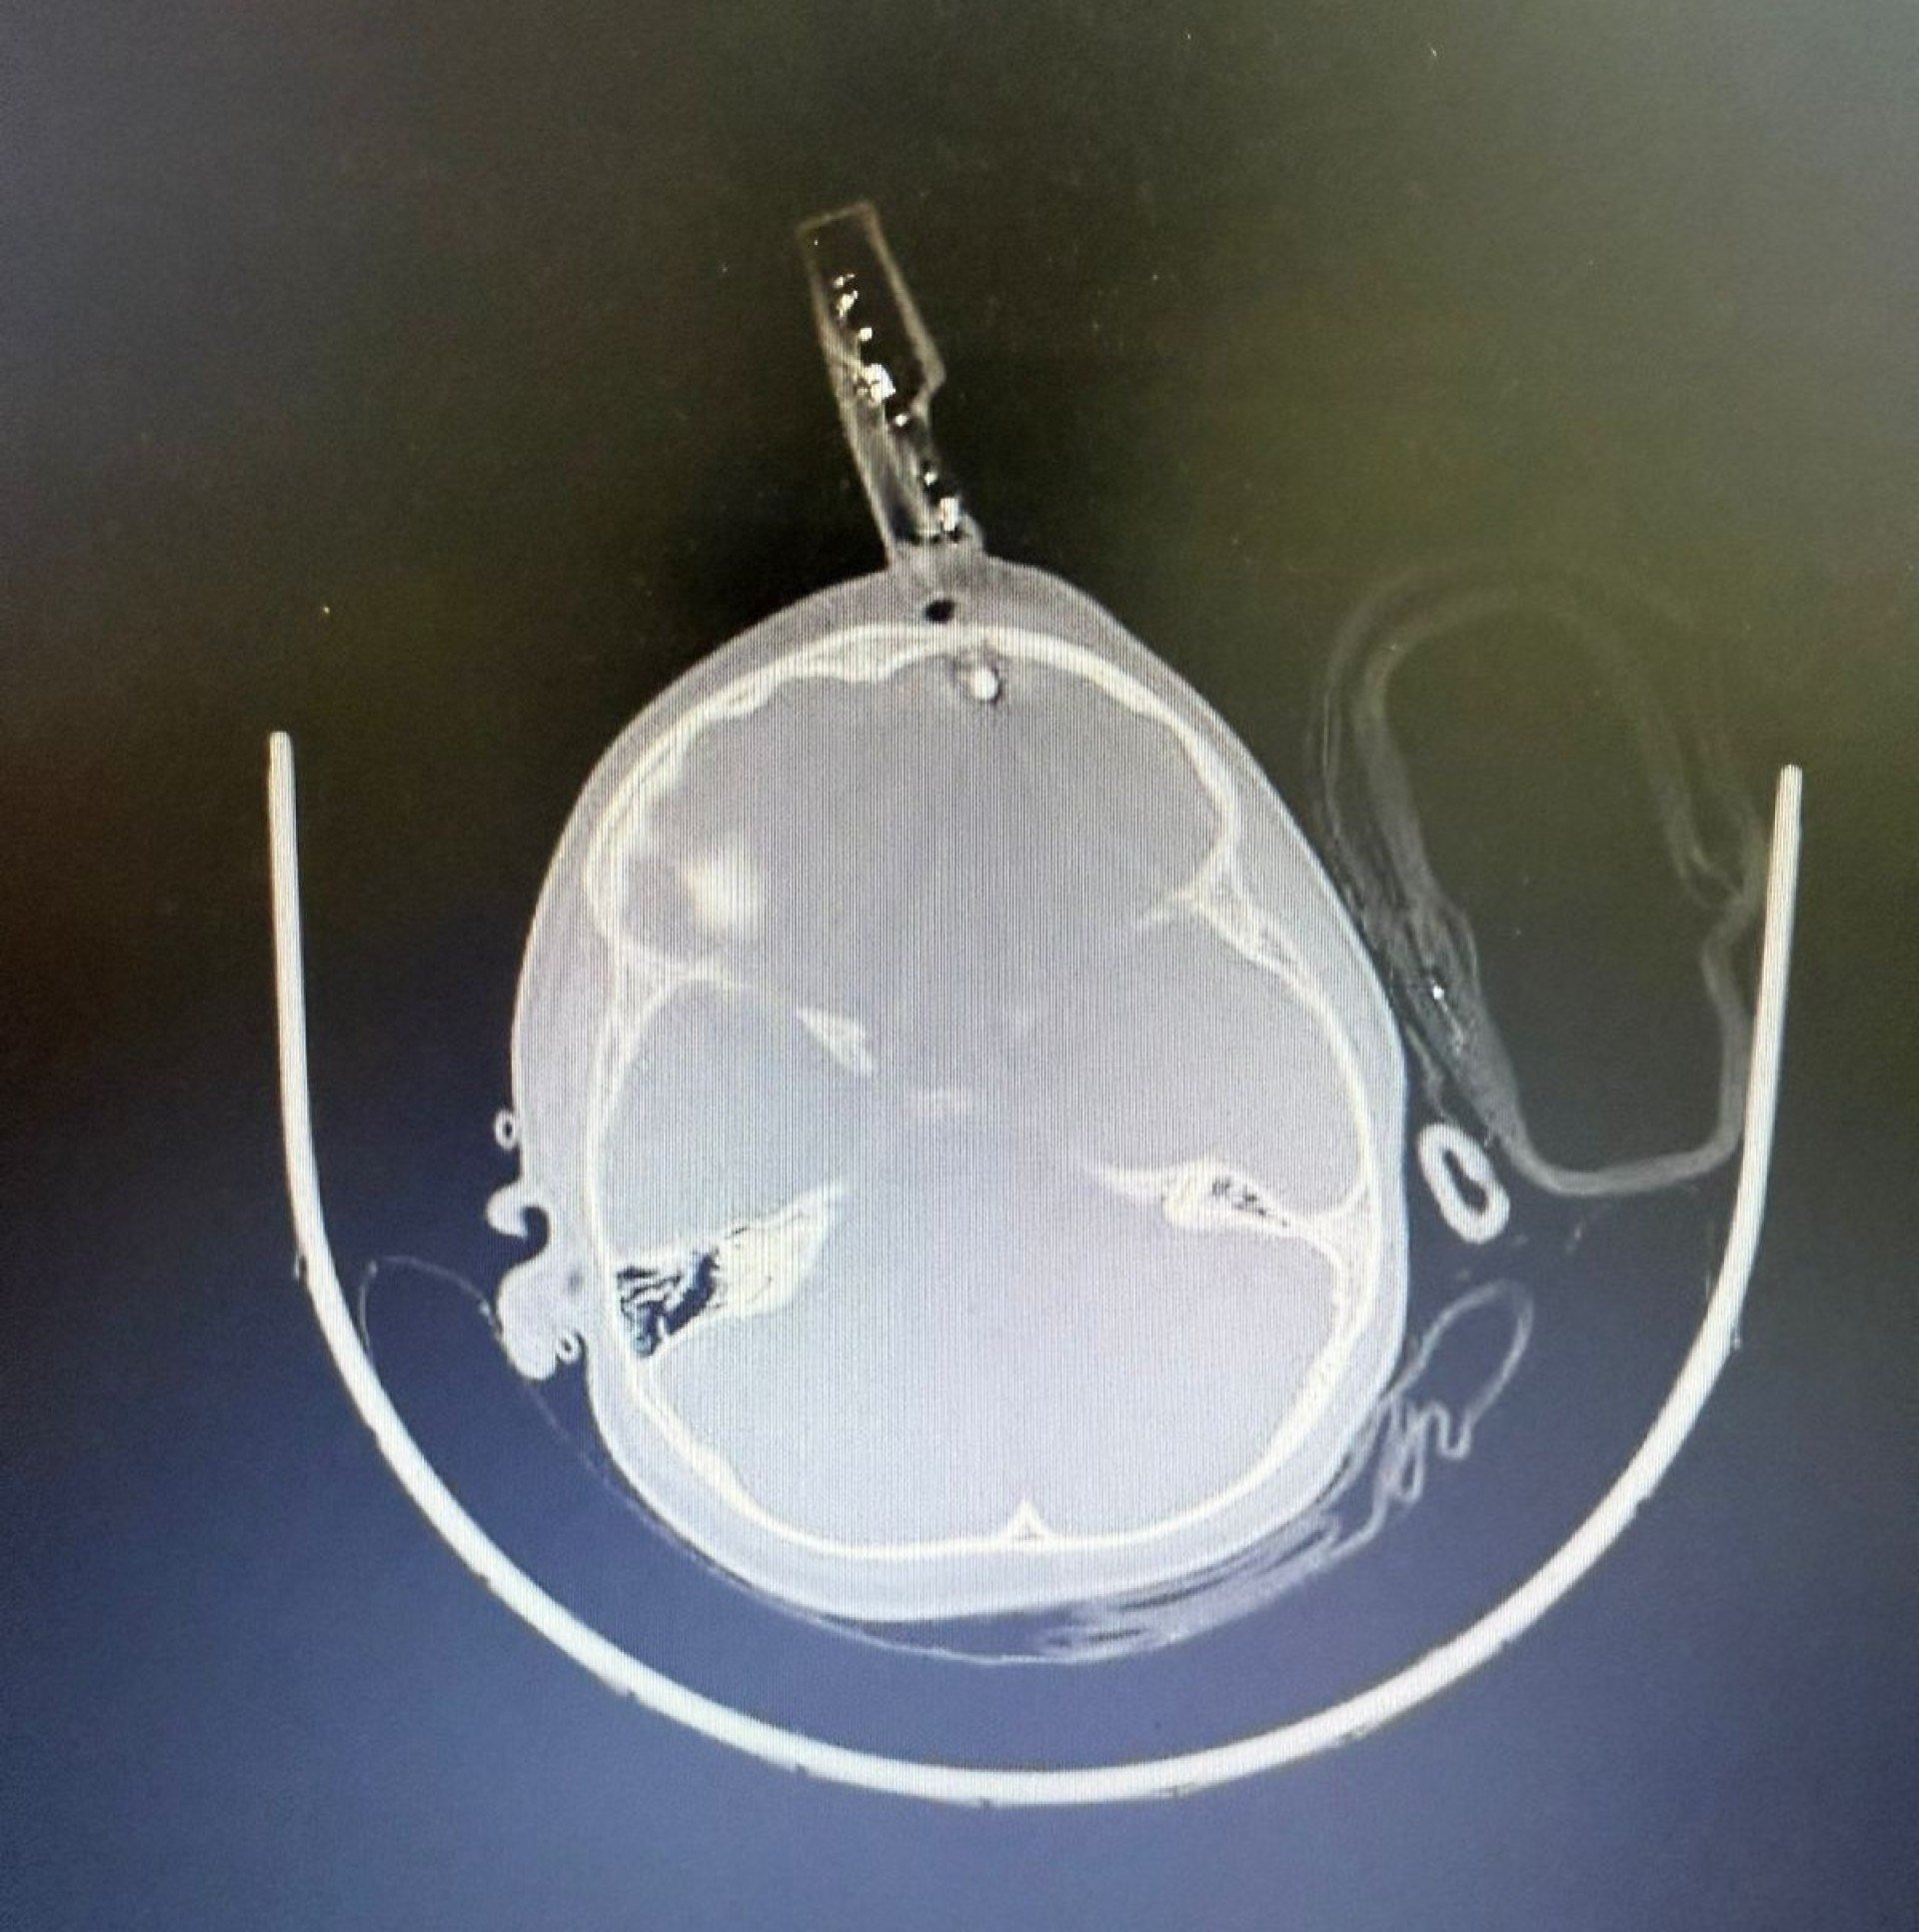

A criança foi levada inicialmente para a UPA de Divinópolis e, diante da gravidade, transferida pelo Samu para a sala vermelha do Hospital São João de Deus. Exames de imagem confirmaram que o pino havia transfixado o osso do crânio e atingido o cérebro. “O osso do crânio nessa idade é muito fino, tem apenas alguns milímetros. Pela tomografia, vimos que o objeto atravessou a calota craniana e lesionou a ponta do lobo frontal”, detalhou Bruno Castro.

Apesar da gravidade do ferimento, a criança estava consciente e foi levada imediatamente ao centro cirúrgico. O procedimento ocorreu sem intercorrências. “Foi uma cirurgia rápida e tranquila. Retiramos o corpo estranho, estancamos um pequeno sangramento e fizemos a correção da lesão. Ela acordou bem da anestesia e foi encaminhada ao CTI pediátrico”, afirmou o neurocirurgião.

A criança permaneceu 36 horas em observação intensiva e, após nova tomografia sem sinais de sangramento intracraniano, seguiu para a enfermaria. Por protocolo, recebeu antibiótico venoso durante cinco dias para prevenir infecções.